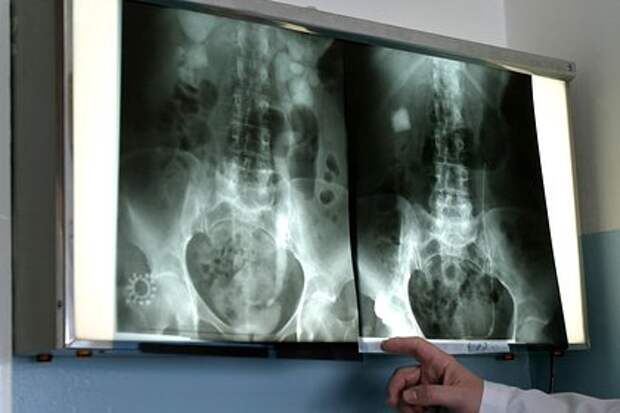

У подростка из Москвы чуть не взорвалась почка